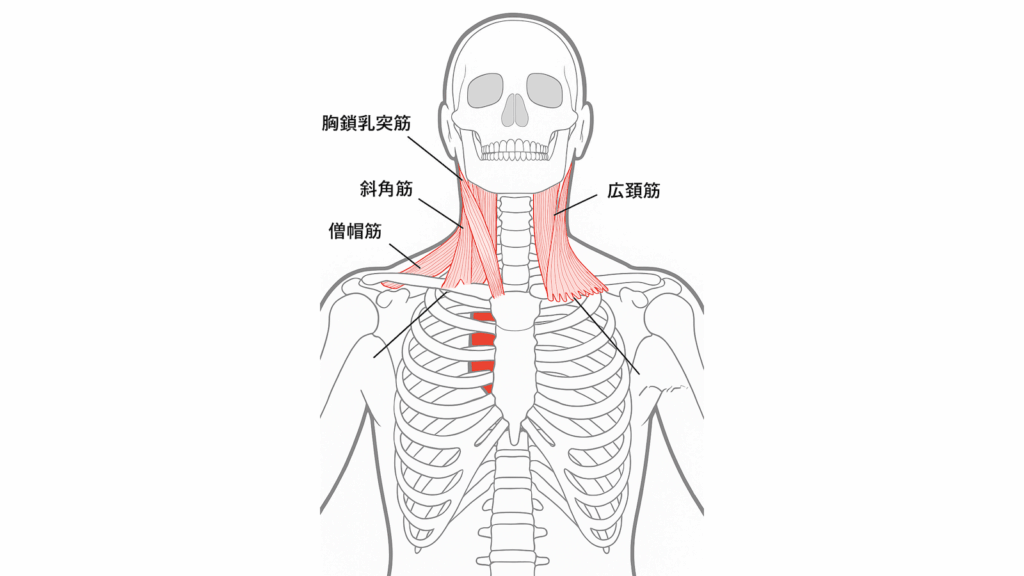

食いしばり・歯ぎしりがあると、

- 胸鎖乳突筋

- 斜角筋

- 広頚筋

といった、耳〜鎖骨の下(第一肋骨)にかけて走る筋肉が強く緊張します。

これらの筋肉が縮こまることで、

- 顔が下を向いた姿勢

- 首が前に倒れた状態(ストレートネック傾向)

になりやすくなります。

その姿勢では奥歯が噛み合いやすくなり、 さらに首の前の筋肉・咬筋・側頭筋が緊張 → 食いしばりが助長される という悪循環に陥ります。

特に側頭筋(こめかみにある筋肉)は、

- こめかみを走る神経(三叉神経の枝)

- 血管(浅側頭動脈)

を圧迫するため、側頭部(こめかみ)の頭痛を引き起こすこともあります。

※解剖学アプリを使用し、筆者が作成した画像です

- 首の前(斜角筋・胸鎖乳突筋・広頚筋)